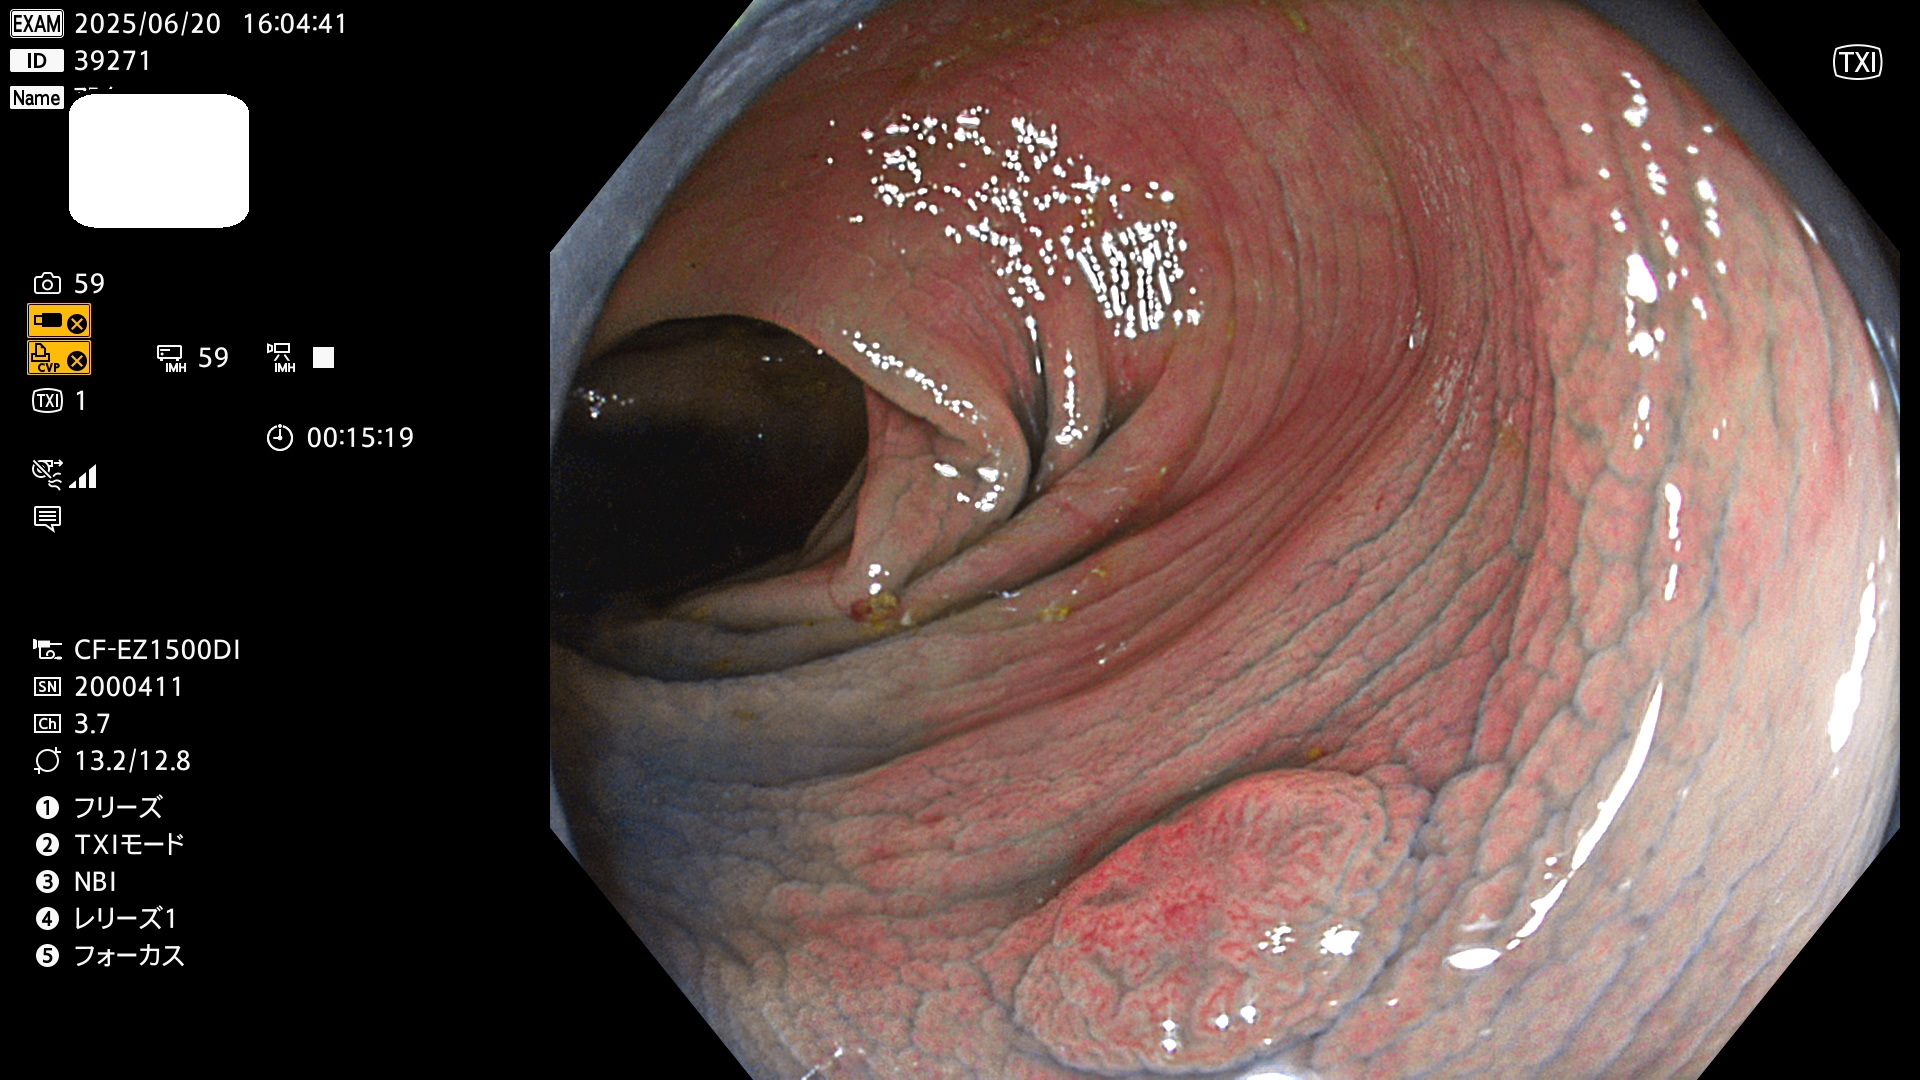

今週のUb、Uc型腺腫

完全に平坦な物をUb、陥凹している物をUcと呼びます。Ubは認識が困難で、Ucはびらん(炎症)と紛らわしいために見落とされやすく、「内視鏡後・大腸癌」の原因になります。

抽出の対象期間 2025年6月19日〜6月22日の4日間(48件の検査)10個 (10/48=20%)